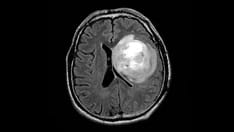

T1-weighted axial gadolinium-enhanced MRI demonstrates an enhancing tumor of the right frontal lobe. Image courtesy of George Jallo, MD.